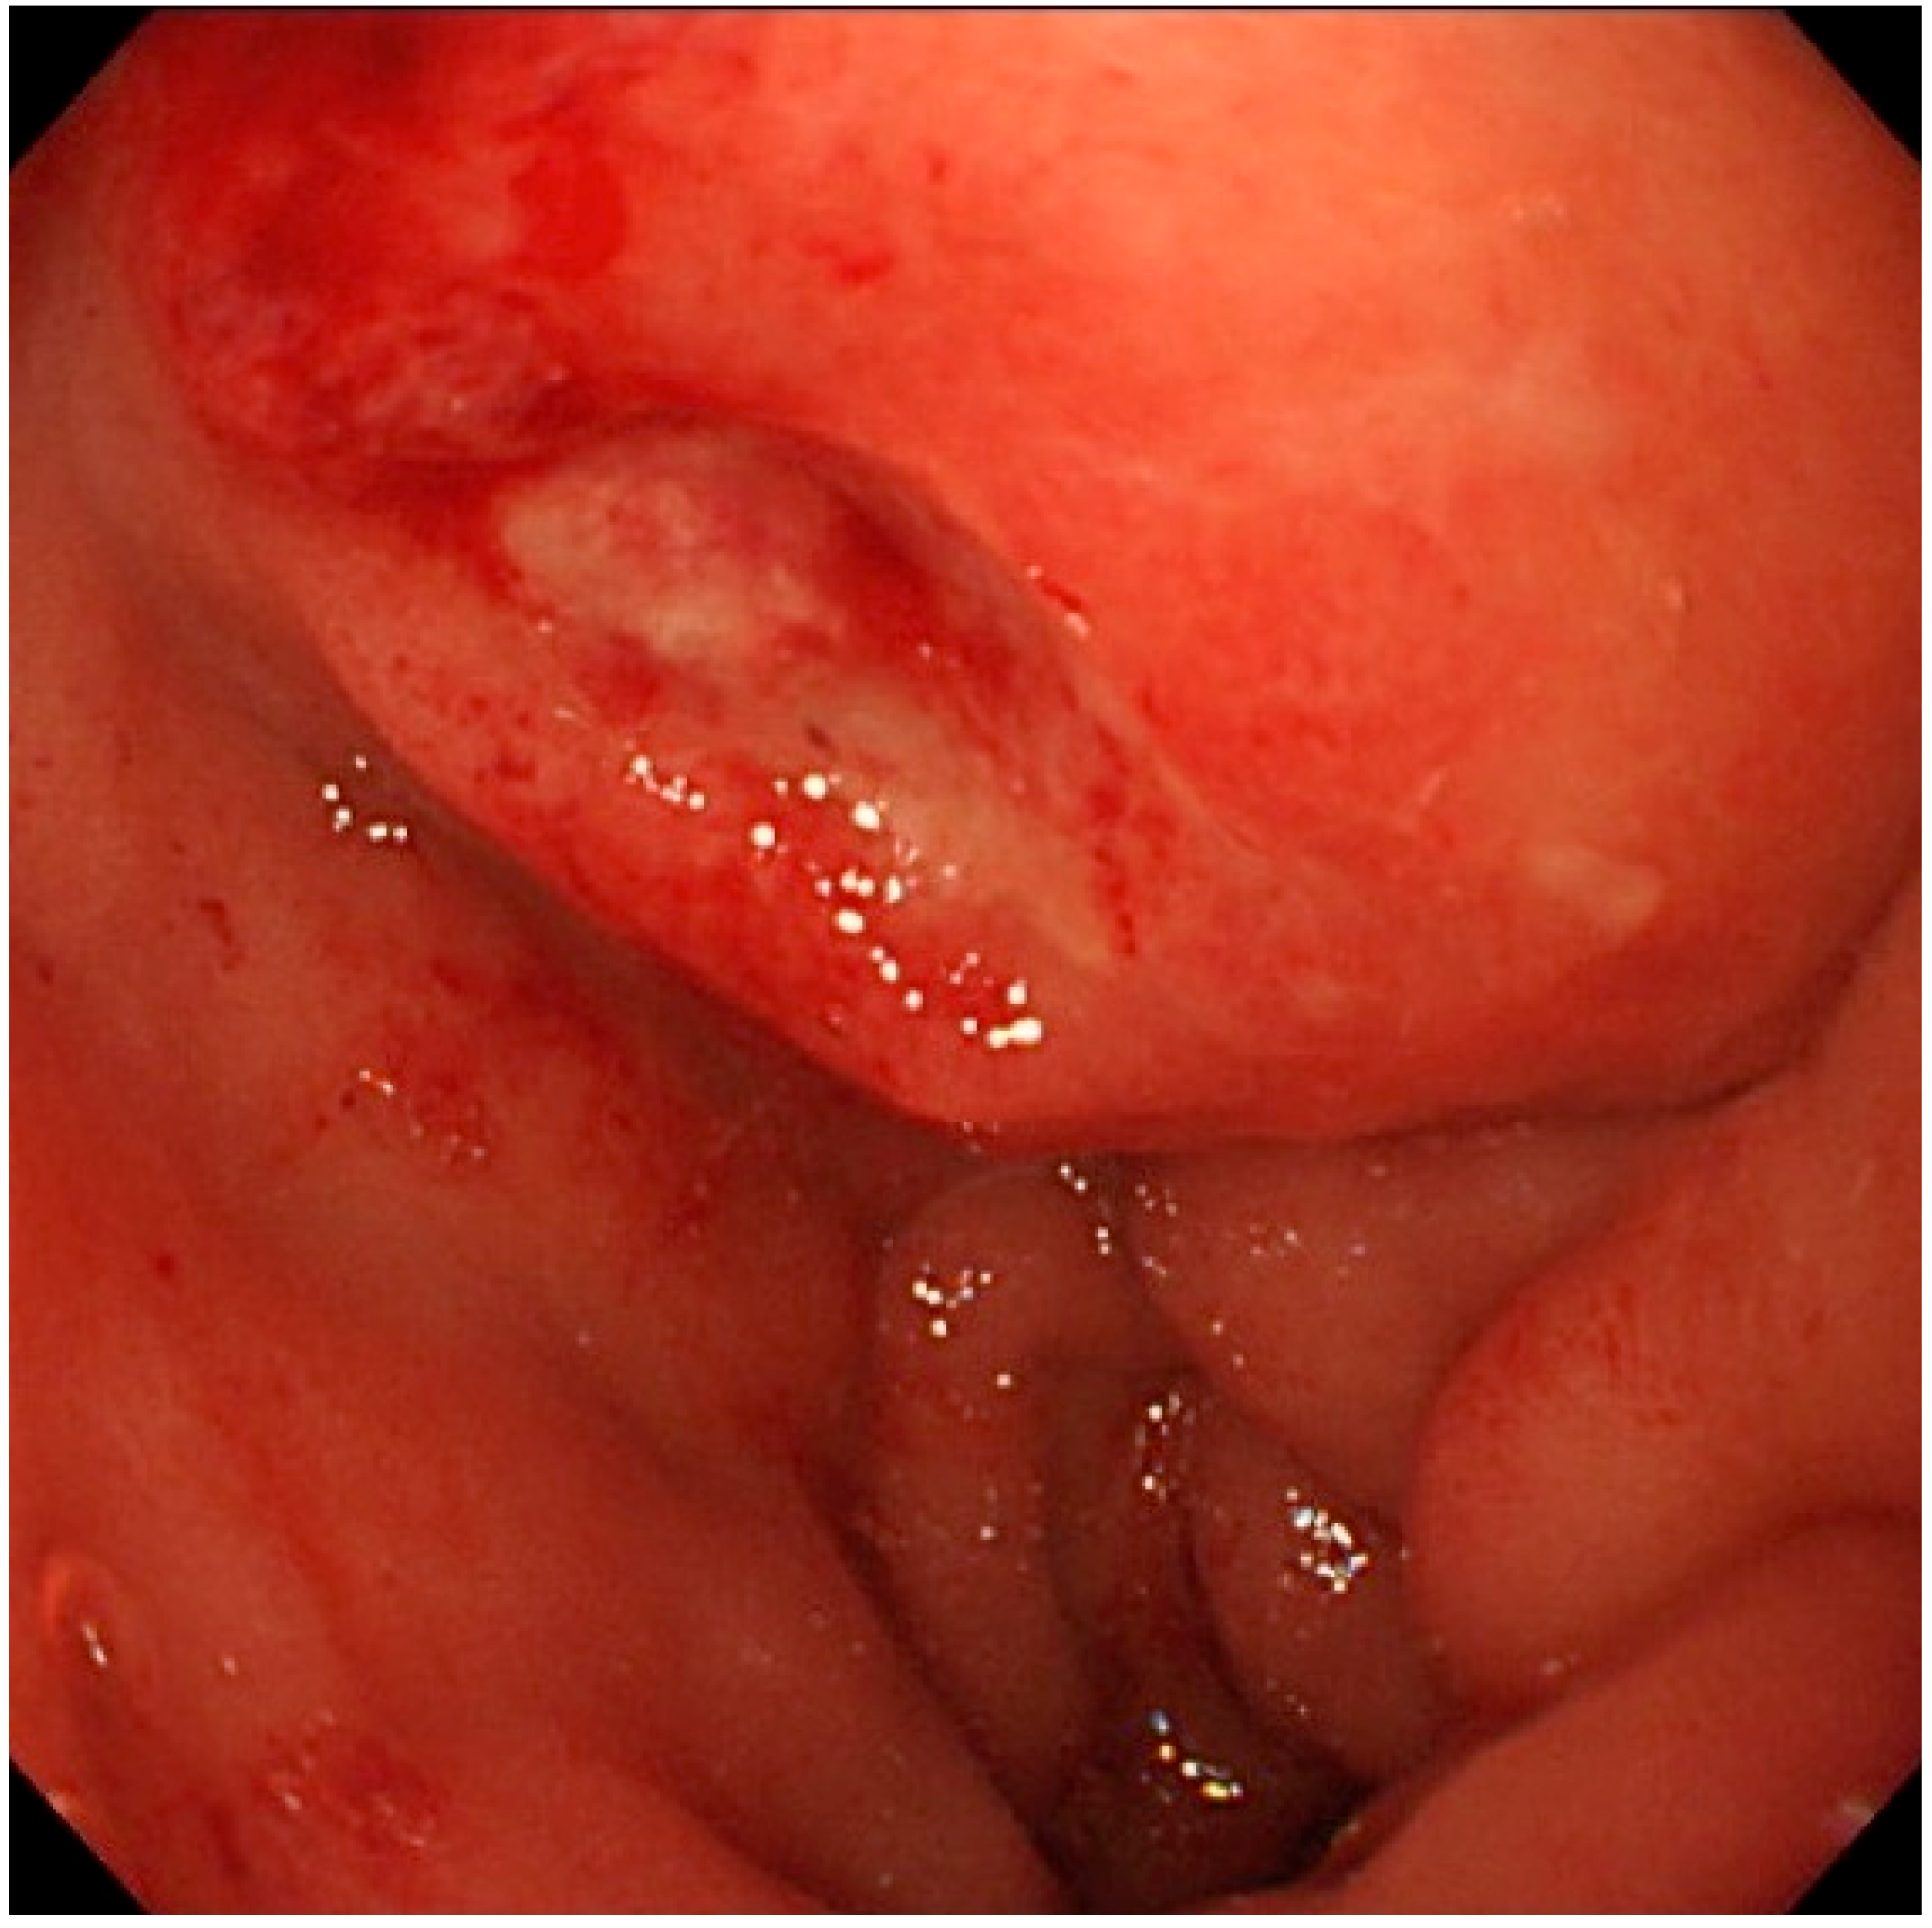

2. Case Presentation